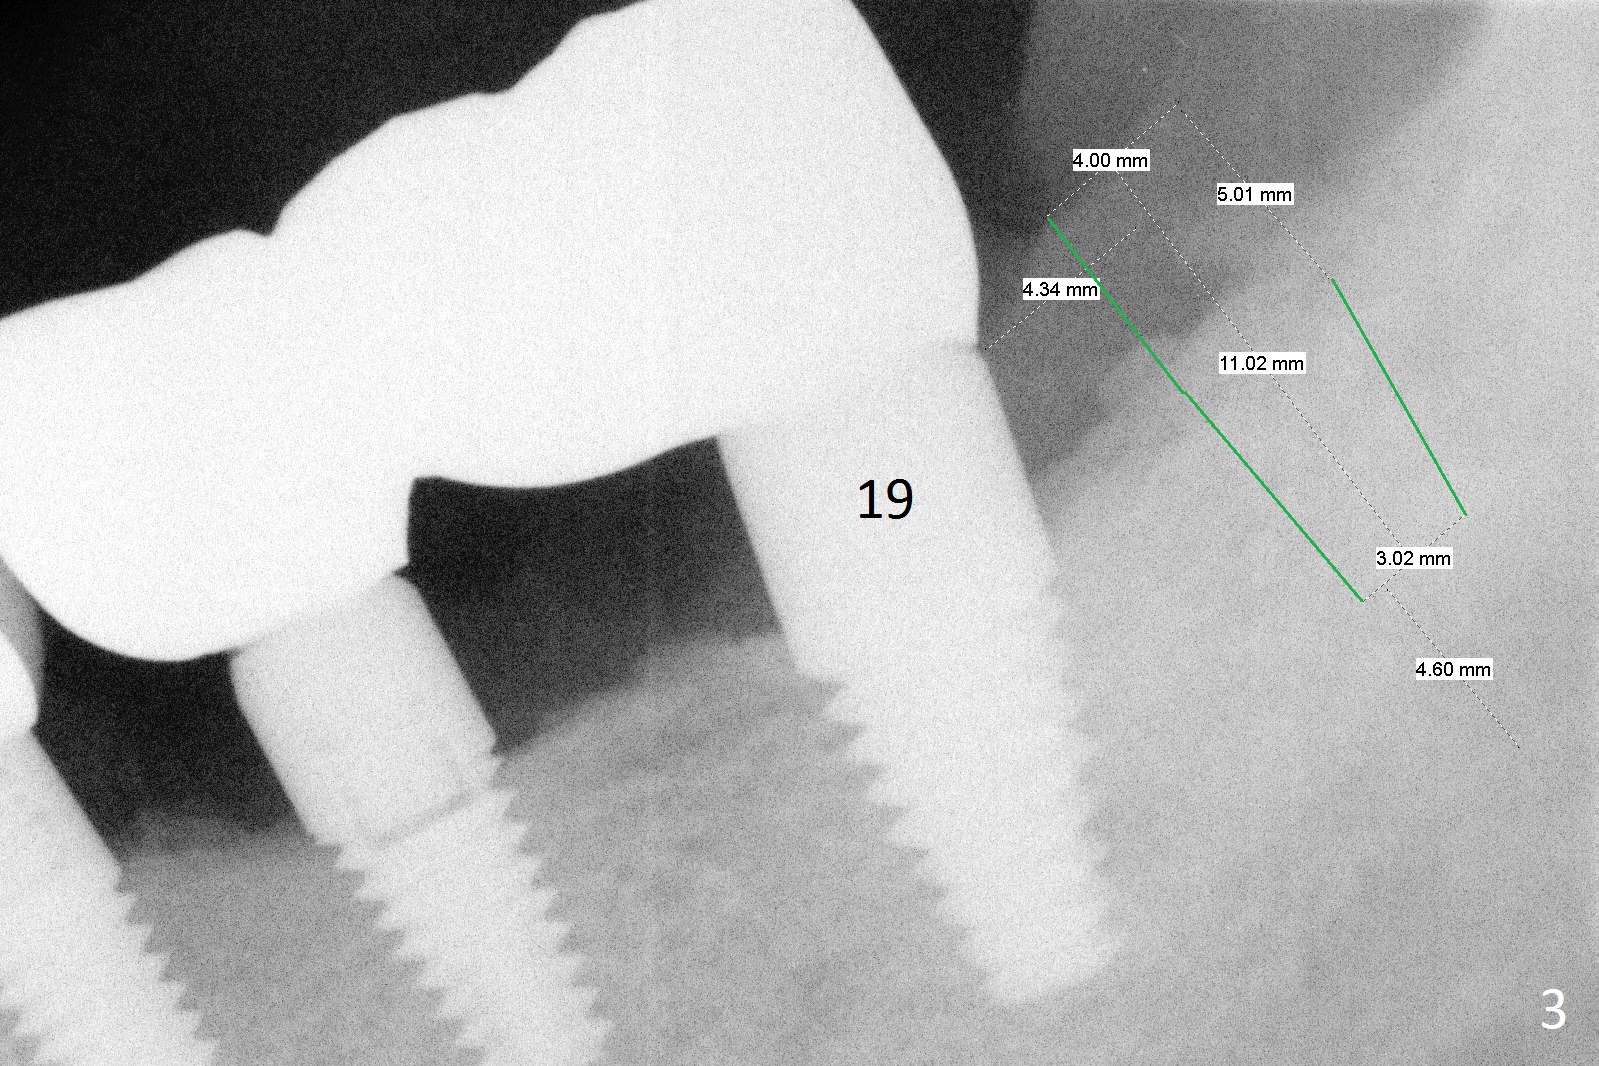

A 58-year-old man has two types of implant complications: periimplantitis at #4 (in spite of 2 bone graft surgeries, Fig.1) and abutment loosening at #14 and repeatedly 19 (probably due to bruxism, Fig.2,3).

To overcome bruxism, implants will be placed at the 2nd molar sites (total 4). Since the implant at #19 was placed distal, the crowns at #18 and 19 will be splinted. The unipost at #14 is 6 mm, 10º cemented with Ketac (implant 8x14 mm). To increase retention, use bonding and place 1 or 2 heavy retention grooves or use a straight abutment. If the existing abutment cannot be removed, enlarge the retention groove and bury a piece of wire in the groove with bonding. The last resort will be splinting with #15.